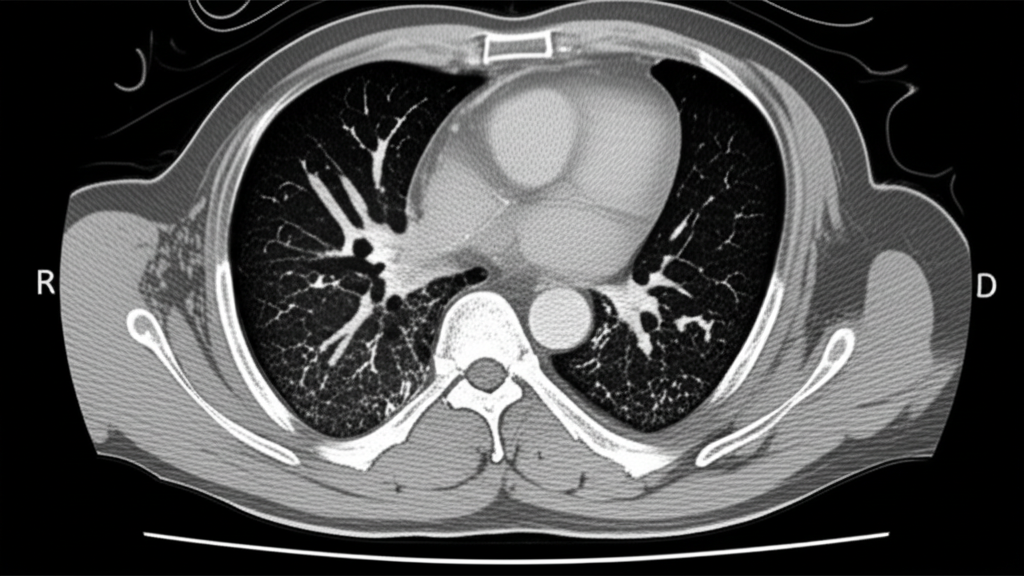

폐 CT는 폐 질환 진단에 매우 중요한 역할을 하는 영상 검사입니다. 흉부 X선 검사보다 훨씬 더 자세한 정보를 제공하여 폐암, 폐렴, 만성 폐쇄성 폐질환(COPD) 등 다양한 질환을 조기에 발견하고 정확하게 진단하는 데 도움을 줍니다. 건강 검진 시 폐 CT 검사를 고려하는 것은 건강한 삶을 유지하는 데 매우 현명한 선택입니다.

폐 CT로 알 수 있는 것은 폐암뿐만 아니라 폐렴, 결핵, 기관지확장증, 간질성 폐질환 등 다양한 폐 질환을 진단하는 데 유용합니다. 이러한 질환들은 호흡 곤란, 기침, 가래 등의 증상을 유발할 수 있으며, 심한 경우 생명을 위협할 수도 있습니다. 폐 CT 검사를 통해 이러한 질환들을 조기에 발견하고 적절한 치료를 받으면 질병의 진행을 늦추고 합병증을 예방할 수 있습니다.

폐 CT는 폐암의 크기, 위치, 림프절 전이 여부 등을 정확하게 파악하여 병기를 결정하는 데 중요한 역할을 합니다. 조기 폐암의 경우 수술적 절제를 통해 완치를 기대할 수 있으며, 폐 CT는 이러한 조기 진단에 결정적인 기여를 합니다.

폐 CT는 폐렴의 종류와 범위를 파악하고, 합병증 발생 여부를 확인하는 데 유용합니다. 특히 면역력이 약한 환자나 노인의 경우, 폐렴이 심각한 합병증으로 이어질 수 있으므로 폐 CT 검사를 통해 정확한 진단과 치료 계획을 수립하는 것이 중요합니다.

폐 CT는 COPD 환자의 폐기종 정도, 기관지 확장 여부, 폐렴 발생 여부 등을 평가하는 데 사용됩니다. 이를 통해 COPD의 진행 정도를 파악하고, 적절한 치료 계획을 수립하여 환자의 삶의 질을 향상시킬 수 있습니다.

폐 CT는 결핵 병변의 위치, 크기, 공동 형성 여부 등을 파악하는 데 유용합니다. 특히 흉부 X선 검사에서 발견하기 어려운 초기 결핵 병변을 발견하는 데 도움이 되며, 약물 치료 효과를 평가하는 데에도 활용됩니다.

폐 CT는 간질성 폐질환의 종류와 범위를 파악하고, 질병의 진행 정도를 평가하는 데 중요한 역할을 합니다. 간질성 폐질환은 폐 섬유화를 유발하여 호흡 곤란을 악화시킬 수 있으므로, 폐 CT 검사를 통해 조기에 진단하고 적절한 치료를 받는 것이 중요합니다.